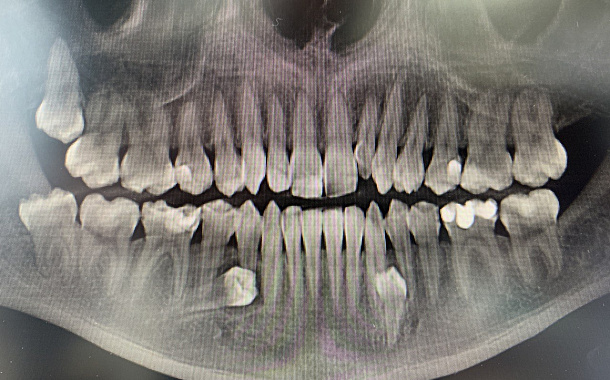

Комплексное лечение: ортодонтическое, хирургическое, ортопедическое

Пациентка обратилась с жалобами на неровные передние зубы.

При осмотре выявлено-сужение верхнего и нижнего зубных рядов, скученное положение зубов обеих челюстей, рецессия десны. КТ показала убыль костной ткани в области зубов на нижней челюсти на 50%.

Предложено комплексное лечение.

Узнать подробнее